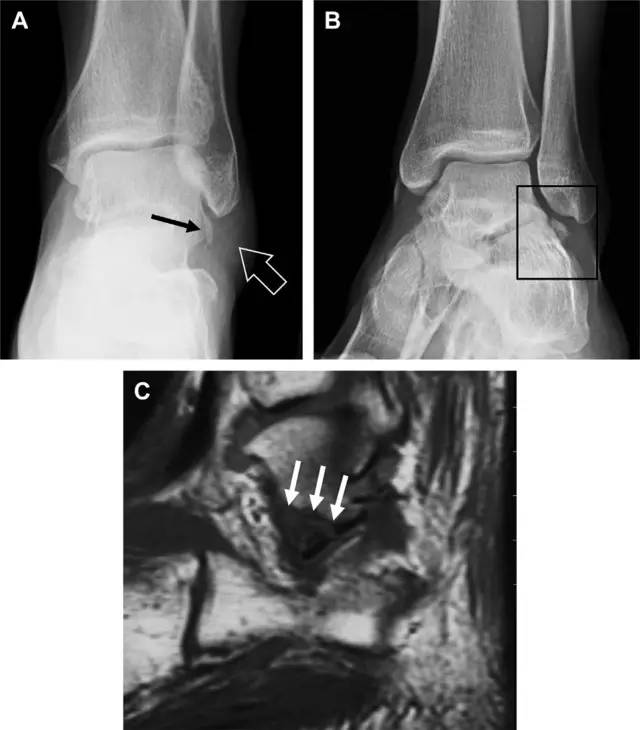

16 胫骨后踝骨折

涉及到三角韧带和外侧副韧带(LCL)的复杂性骨折常常不难发现,尤其是存在表面软组织肿胀时。然而,后胫腓韧带牵拉引起的胫骨后踝骨折则很难发现。这些骨折大小不一(图 2),却很重要,因为他们常与胫骨远端螺旋骨折有关,或者是三踝骨折的一部分。

图 2 胫骨后踝骨折。A 侧位片示来源于胫骨后踝的一个小骨折碎片(箭头),因踝部扭伤导致;B 另一位跖屈损伤的患者,侧位片示一个大骨折块(箭头)